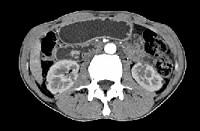

问题 男,48岁,进行性黄疸,发热,腹胀,影像检查如图,最佳的诊断是()

选项 A.胆总管囊肿 B.胆总管结石 C.胆总管癌 D.十二指肠乳头癌 E.胰头癌

答案 D